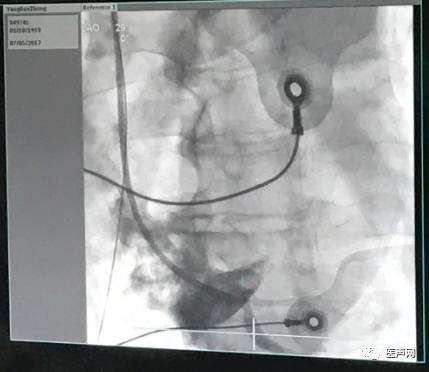

本例患者药物治疗9年无效,LVEF〈 26%,左室壁整体运动减低,全心增大室性早搏,左束支阻滞形,QRS〉136MS左室扩大。动态心电图(2017-6-26)显示窦性心律,房性心律失常总心博数为128次占心率的0.111%,室性心律失常总心搏数为5431次,占总心率的4.689%。患者左侧锁骨下造影发现患者为永存左上腔,左锁骨下静脉汇入冠状经脉窦,并与右侧锁骨下静脉无交通分支,右侧外周静脉周围血管造影,患者右锁骨下静脉经右上腔静脉汇入右房。决定经右侧植入CRT进行心脏再同步化治疗,最终顺利完成手术。

心脏彩超提示,左室壁整体运动减低、全心增大、主动脉窦部稍微增宽、肺动脉稍微增宽、二尖瓣中量反流、主动脉瓣少量偏多反流、三尖瓣少量反流,左心室收缩功能低下(LVEF〈 26% )。12导联心电图显示窦性心动过速、室性早搏、左束支阻滞形、QRS〉136MS,R波上升不良;ST段异常,未见明显T波改变。BNP:1286ng/L。患者左侧锁骨下造影发现患者为永存左上腔,左锁骨下静脉汇入冠状经脉窦,并与右侧锁骨下静脉无交通分支,右侧外周静脉周围血管造影,患者右锁骨下静脉经右上腔静脉汇入右心房。

该患者心力衰竭反复发作长达9年,患者左侧锁骨下造影发现患者为永存左上腔,左锁骨下静脉汇入冠状经脉窦,并与右侧锁骨下静脉无交通分支,右侧外周静脉周围血管造影,患者右锁骨下静脉经右上腔静脉汇入右心房。,经静脉植入左室电极难度较大,手术风险极高。

通过左室递送系统鞘管6250MPR在右侧经静脉放置起搏右房、右室、左室导线,囊袋制作。

造影图片: